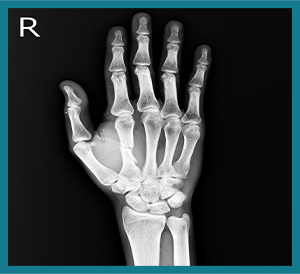

X-ray of hand

Hand